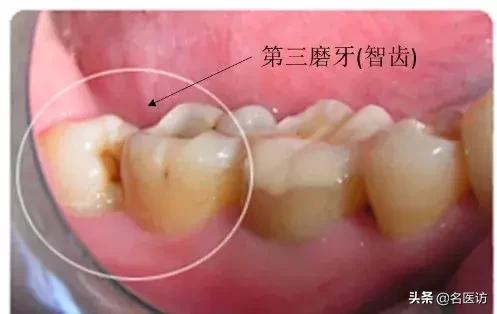

原来,智齿,学名叫第三磨牙,通常在人 17~25 岁时出现在口腔中。大部分人有 4 个智齿(上颌 2 个,下颌 2 个),但是也有人可能只有 1~3 个甚至没有。

当这些智齿突破牙龈,它们便被称为“萌出”。如果智齿不能萌出,或只能部分萌出牙龈,就叫做“阻生”。

阻生智齿很常见,一般来说是不痛的。需要注意的是,无论智齿是否萌出,如果不认真使用牙刷、牙线清洁牙齿,没有定期看牙医的话,智齿可能会引起问题,比如肿痛等。